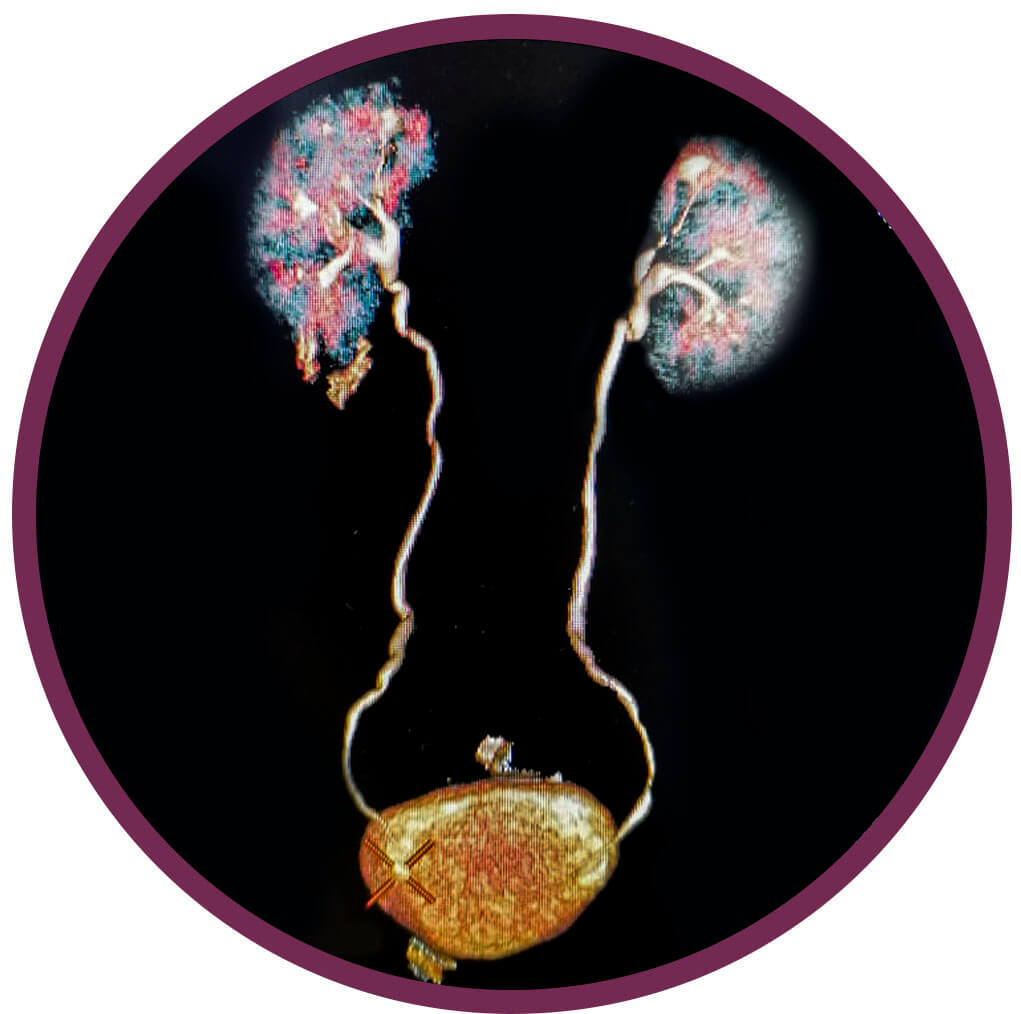

CT urográfia

Milyen előkészület szükséges?

A CT vizsgálat előtt fontos a kezelőorvossal, családorvossal, belgyógyász szakorvossal vagy urológus szakorvossal történő konzultáció, hisz a CT vizsgálat során, sugárterhelés és jódtartalmú kontrasztanyag adása történik, így a vizsgálatot csak orvosi javaslat alapján végezzük. Mindig érdemes a vizsgálatra úgy készülni, hogy bizonyos esetekben legyen lehetőség kontrasztanyag adására is, ezért a vizsgálat előtt 6 órával már nem szabad enni. A kontrasztanyag adása előtt meg kell vizsgálni a vese működését jelző labor paramétereket, mivel súlyosan károsodott (beszűkült) vesefunkció esetén a kontrasztanyag adása lehetőség szerint elkerülendő. Ismert kontrasztanyag allergia esetén a kontrasztanyag adása tilos (kontraindikált). A kontrasztos vizsgálatok előtt a metformin tartalmú cukorbetegségben adott gyógyszerek szedését be kell szűntetni.

Hogyan végezzük a vizsgálatot?

A CT-készülékünk egy nagy, vastag gyűrűhöz hasonlít, melynek aljában egy asztal van, ami mozog. Ön ezen az asztalon fekszik mozdulatlanul, miközben a felvételeket készítünk. A vizsgálószerkezet működése közben zúgó, búgó hangot ad ki, de ettől nem kell megijedni, hisz a vizsgálat fájdalommentes

Mi a vizsgálat lényege?

A CT urográfia egy olyan speciális kontaszts has és kismedence CT vizsgálat, melynek során késői, a kontrasztos húgyutakban történő kiválasztódását is leképező felvételsorozatok is készülnek, így a húgyutak kiválasztórendszerében (vesemedence, hugyvezeték, hugyhólyag, hugycső) bármilyen tágulat vagy szűkület, érleszorítás, kövesség illetve elfolyási akadály pontos megítélésére szolgál. A CT urográfia célja, hogy vesegöcs, vesekő vagy vizelet elfolyási akadály gyanúja esetén láthatóvá tegye a vesék üregrendszerét, a húgyvezetéket és a húgyhólyagot

Van mellékhatása?

A CT urográfia izsgálat előtt fontos a kezelőorvossal, családorvossal, belgyógyász szakorvossal vagy urológus szakorvossal történő konzultáció, hisz a CT vizsgálat során, sugárterhelés illetve kontrasztanyag adása történik, így a vizsgálatot csak orvosi javaslat alapján végezzük. A kontrasztanyag adása a CT urográfia elengedhetetlen alapja, ezért a vizsgálat előtt 6 órával már nem szabad enni. A kontrasztanyag adása előtt meg kell vizsgálni a vese működését jelző labor paramétereket, mivel súlyosan károsodott (beszűkült) vesefunkció esetén a kontrasztanyag adása lehetőség szerint elkerülendő. Ismert kontrasztanyag allergia esetén a kontrasztanyag adása tilos (kontraindikált). A kontrasztos vizsgálatok előtt a metformin tartalmú cukorbetegségben adott gyógyszerek szedését be kell szűntetni.